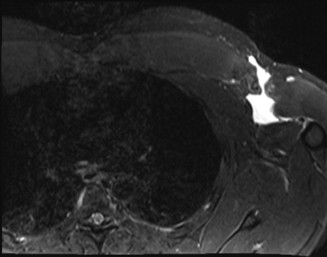

The correct answer is (B). A pectoralis major muscle (PMM) tear or rupture usually occurs in weight-lifters while performing the bench press, but it can occur during

any activity in which the arm is extended and externally rotated while under maximal contraction (eccentric loading force). Patients often present with pain, swelling, ecchymosis, weakness and loss of the axillary fold in the acute setting. In the chronic setting, the swelling and ecchymosis have typically subsided. They may report an audible pop or a tearing sensation. On examination, there can be an apparent continuous muscle or tendon that is mistaken for an intact PMM tendon, but this represents the fascia of the PMM that is continuous with the fascia of both the brachium and the medial antebrachial septum. This continuous fascia will examine as a cord-like structure as shown in Figure 2–78.

Figure 2–78